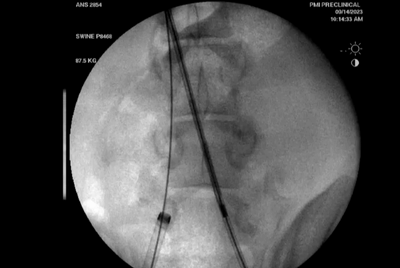

Recana栓塞收集器放置